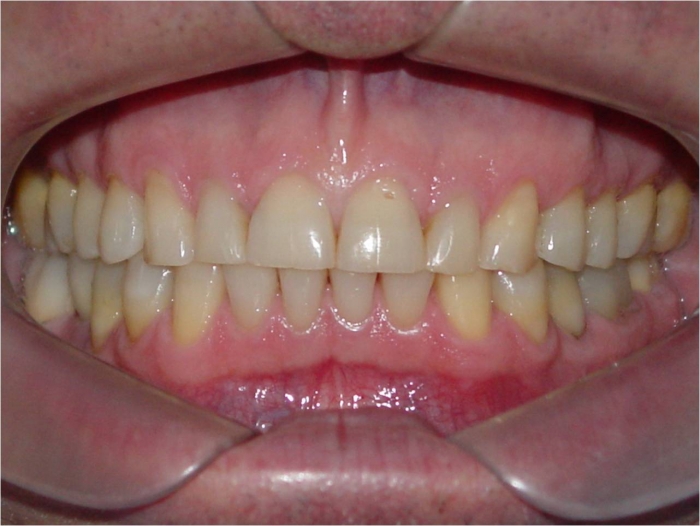

Mordida inicial